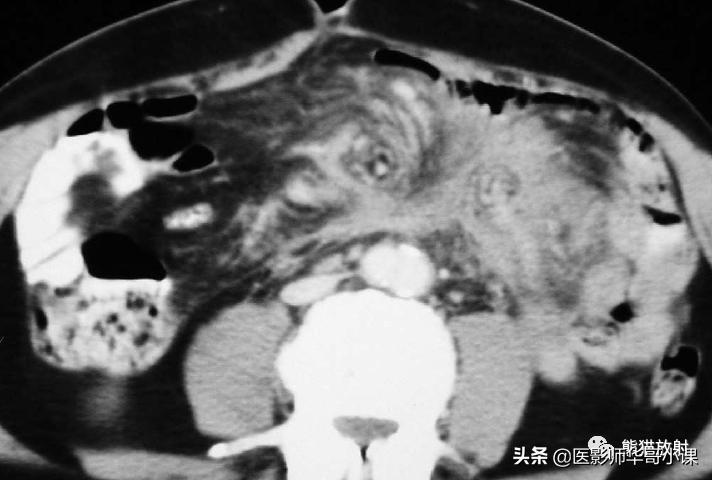

回缩性肠系膜炎CT表现 为浸润性软组织密度肿块,周围可见放射状条索影(图),这些特点可能与纤维瘤病或类癌相似。 硬化性肠系膜炎 在T1WI和T2WI图像上均呈低信号,有助于疾病的鉴别。肿块中央坏死区可见钙化(图)。该病有一定的自限性,通常预后较好。

纤维性肠系膜炎。不明原因发热患者,增强CT显示边缘不规则纤维脂肪样肠系膜肿块包绕肠系膜血管。从肿块到相邻的肠系膜脂肪可见放射状软组织条索影。